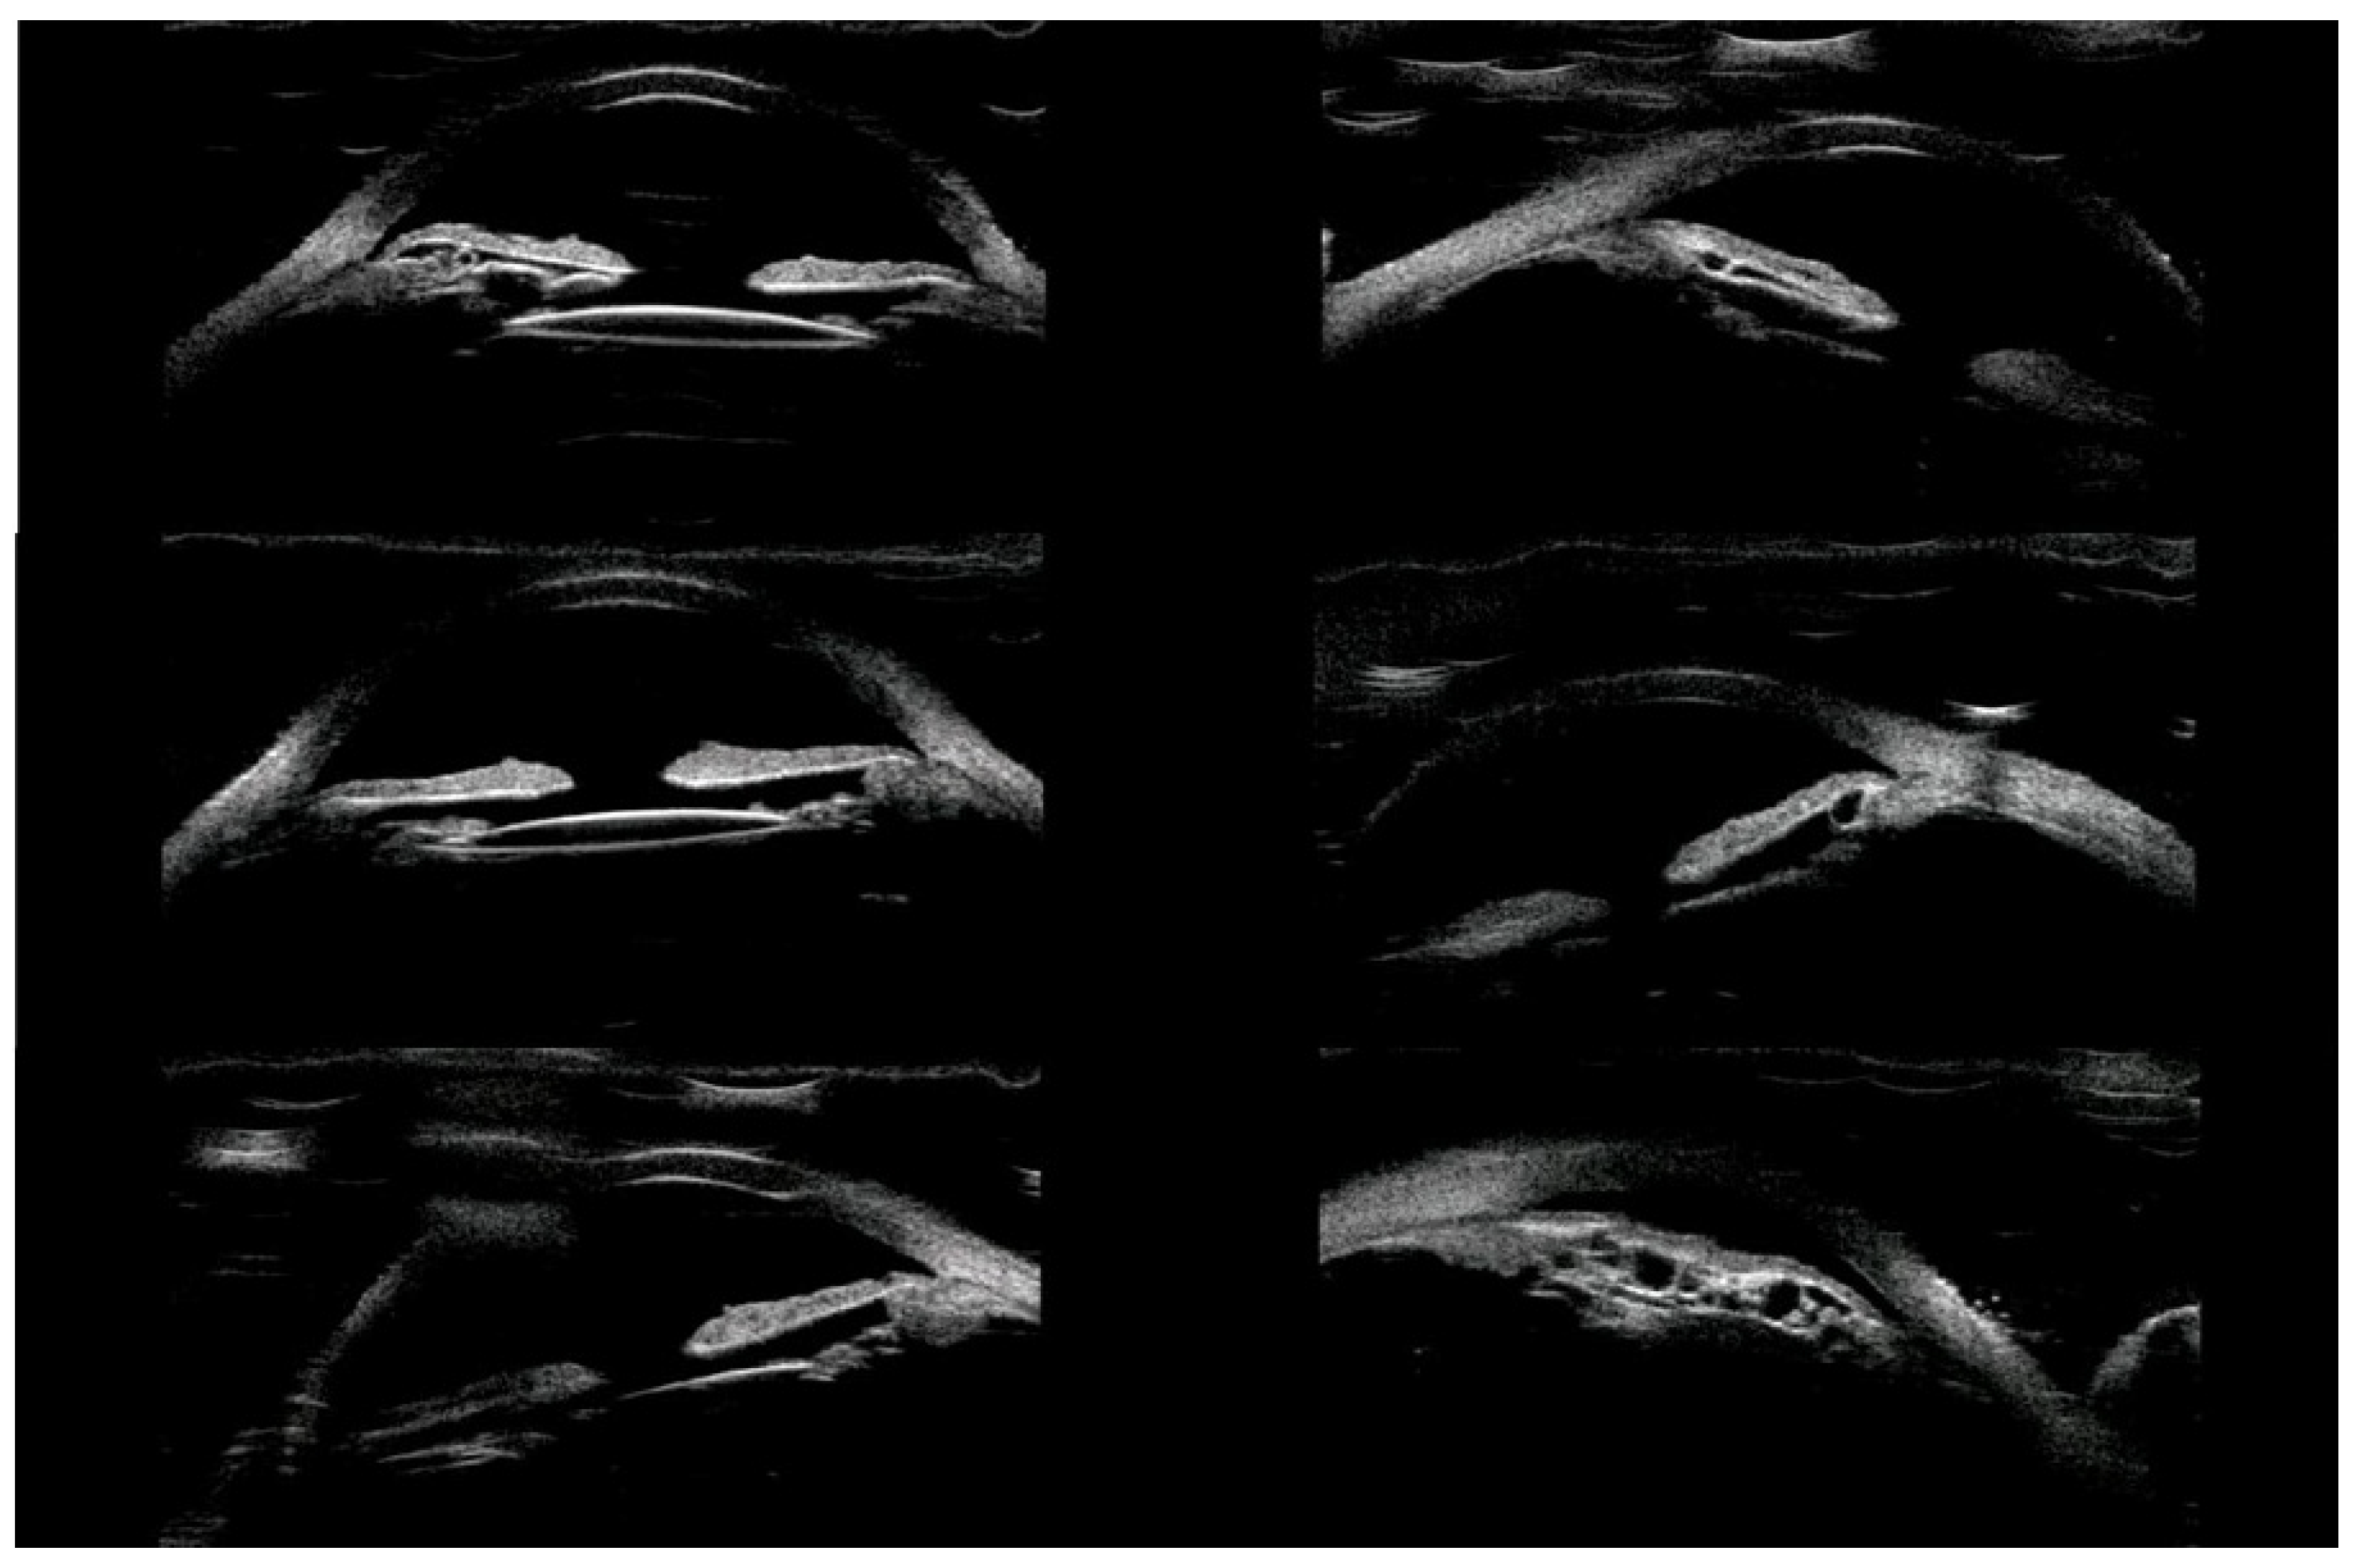

Of the 39 consecutive patients with iris cysts, 27 (69.2%) were women and 12 (30.8%) were men. The mean age at diagnosis was 40.6 ± 17.48 years ranging from 18 to 84 years. The mean age of men and women did not differ significantly and was 41.1 ± 15.6 and 38.2 ± 18.3 years, respectively, p = 0.60. Thirty-four (87.2%) of the cysts were classified as primary and five (12.8%) as secondary. The causes of secondary cysts were as follows: 1—eye injury in childhood, 1—previous cataract surgery using extracapsular cataract extraction, 1—previous phacotrabeculectomy, 2—unknown cause. There were 33 (84.6%) single cysts and 6 (15.4%) multiple cysts (Figure 1, Figure 2 and Figure 3).

In terms of location on the iris, 30 (76.9%) cysts were peripheral, 5 (12.8%) were located at the pupillary margin, 2 (5.1%) were midzonal and 2 (5.1%) were multichamber cysts extending from the periphery to the pupillary margin. We did not observe any free-floating cysts. There were 27 primary and 4 secondary cysts peripheral, 4 primary and 1 secondary at the pupillary edge, and 1 midzonal cyst was primary. A total of 23 (59%) cysts were in the lower temporal quadrant, 11 (28.2%) were in the lower nasal quadrant, and 5 (12.8%) were in the upper nasal quadrant. No cysts were found in the superior temporal quadrant. The cyst walls had moderate to high reflectivity in all cases (Figure 4, Figure 5 and Figure 6).

Figure 1. Small cyst of peripheral iris.

Figure 2. Multichamber cyst.

Figure 3. Multichamber cyst.

Figure 4. Large cyst covering all zones of iris.

Figure 5. Peripheral cyst.

Figure 6. Large peripheral and midzonal cyst.